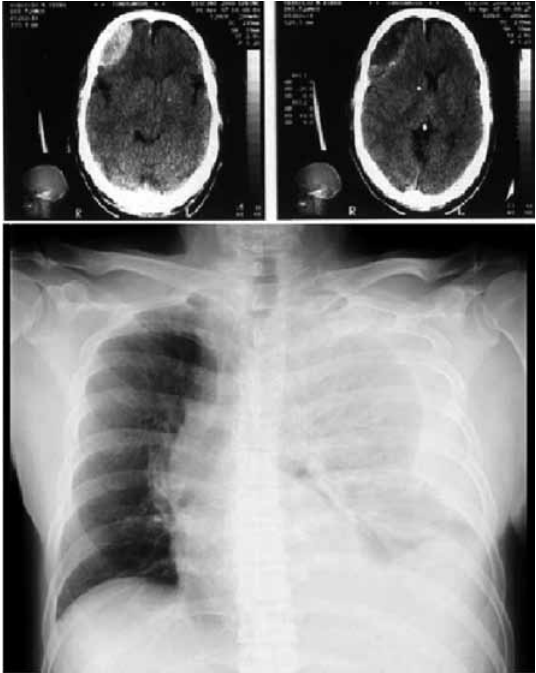

Homem de 48 anos deu entrada na sala de emergência (cerca de 30 minutos após a colisão do ônibus escolar que dirigia) com alteração do nível de consciência (ECG = 10), em hipotensão severa, sem sangramento externo evidente. Após o atendimento inicial, realizado a contento pelo plantonista, obtêm-se os achados tomográficos e radiográficos abaixo demonstrados.

A conduta para com o paciente, sequencialmente, deverá ser: